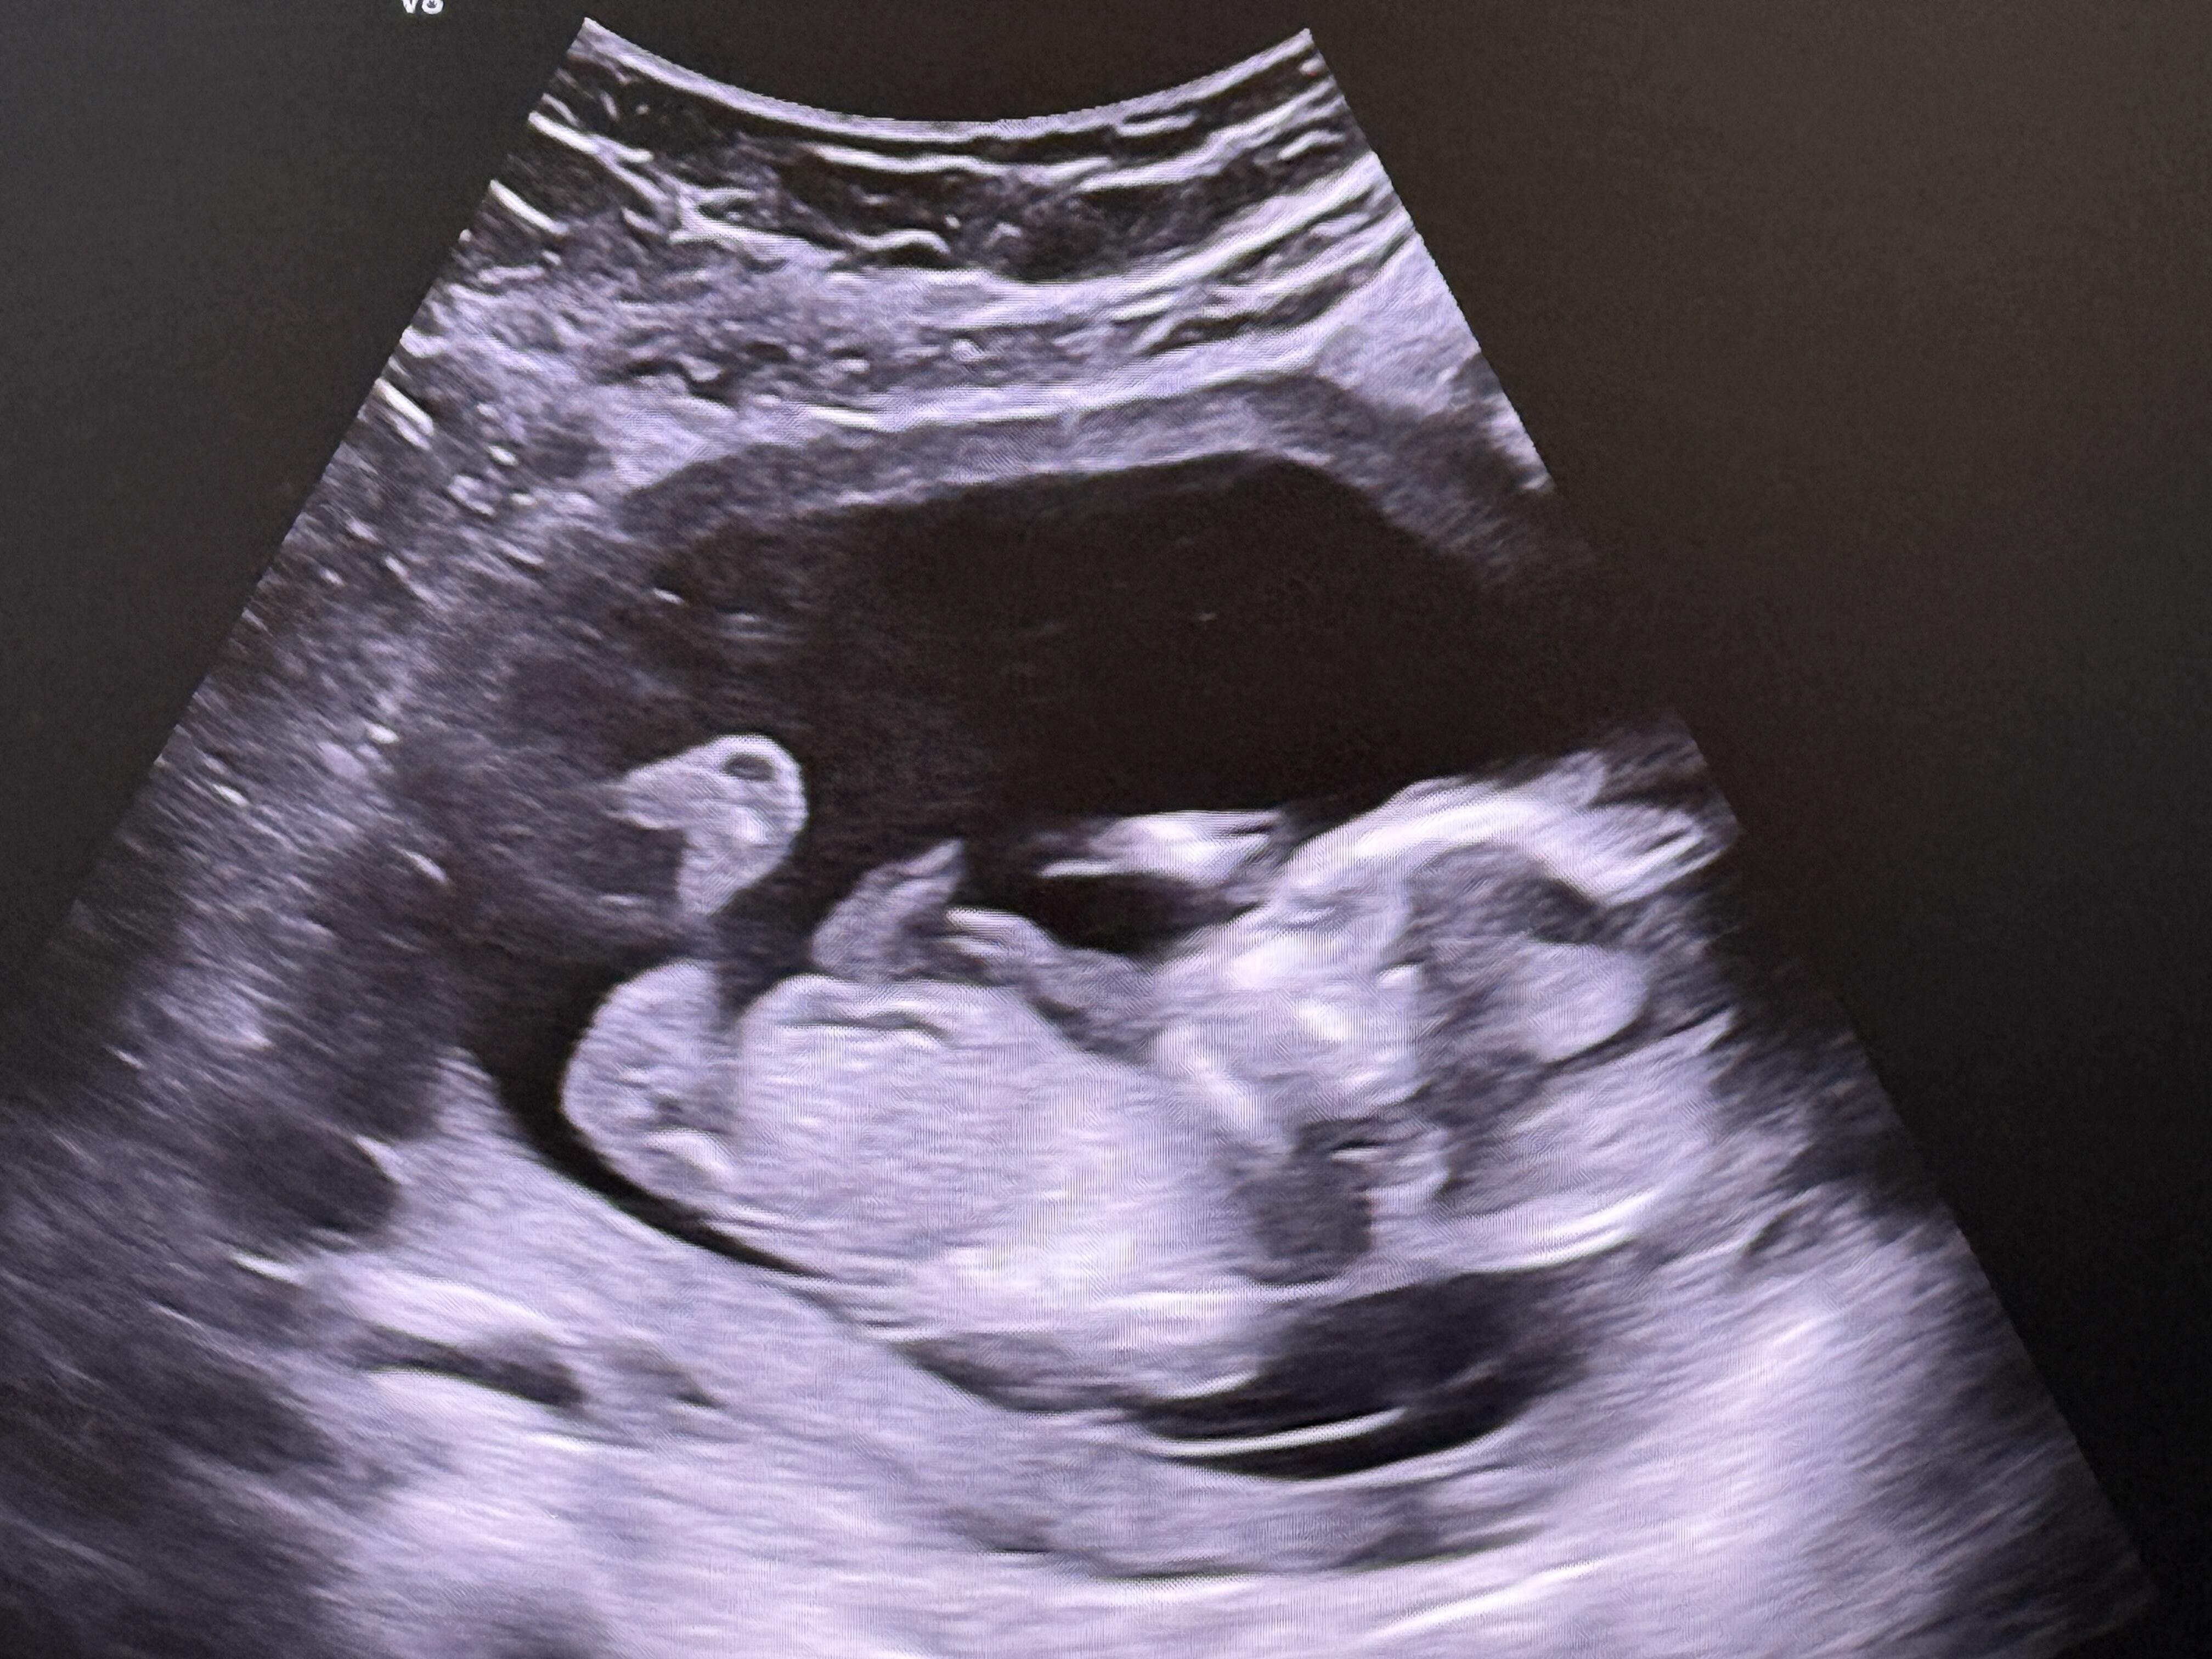

Bacak arası fazla gözükmüyor birde çok net değil ama duruş kız bebek gibi canım farklı net fotoğrafi var mı tekrar at bakayım

Baktım canım ama net fotoğraf atarsa tekrar bakarım

Kese şekli duruşu erkek bebek gibi ama sonraki attığına bir daha baktım kız gibi başka net var mı canım senin ki sürpriz bebek çözemedim ![]()